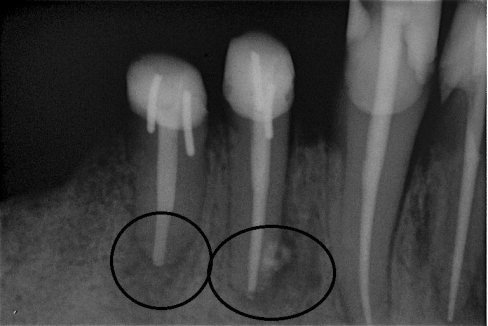

Fallbeispiel für eine große Entzündung an der Wurzel

Wurzel nach erfolgreicher Behandlung 2 Monate später schon fast ausgeheilt

Auch bei einer befriedigenden Wurzelfüllung kann der Erfolg versagt bleiben. Ursachen für Misserfolge sind z. B. wenn zuvor aufgrund einer komplexen Kanalanatomie die Reinigungswirkung zu gering war und dadurch die Kanäle nicht ausreichend von Bakterien befreit werden konnten. In solchen Fällen kann es gelingen, den Zahn durch eine kompromisslose Revision (Wiederholung) der Wurzelkanalbehandlung zu erhalten.

Die endodontische Revision

Im ersten Schritt wird nach der Eröffnung des Zahnes die alte Wurzelfüllung entfernt und es erfolgt die Reinigung des gesamten Systems. Nach dem Reinigen wird für einige Zeit ein desinfizierend und gewebsauflösendes Medikament in den Zahn eingebracht, welches die Desinfektion auch in schwierig erreichbaren Nebenbereichen des Kanalsystems unterstützt.

Sind Reinigung und Desinfektion des Zahnes abgeschlossen, werden die sauberen Kanäle mit der thermoplastischen Obturation 3-dimensional verschlossen. Auch die kleinen Seitenkanäle können so verschlossen werden.